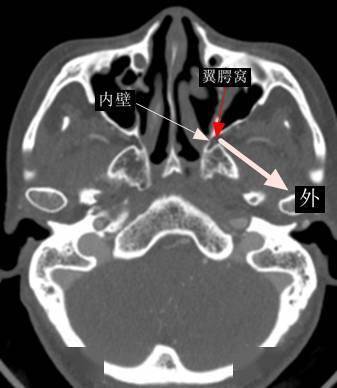

翼腭窝ct

翼腭窝的ct影像解剖